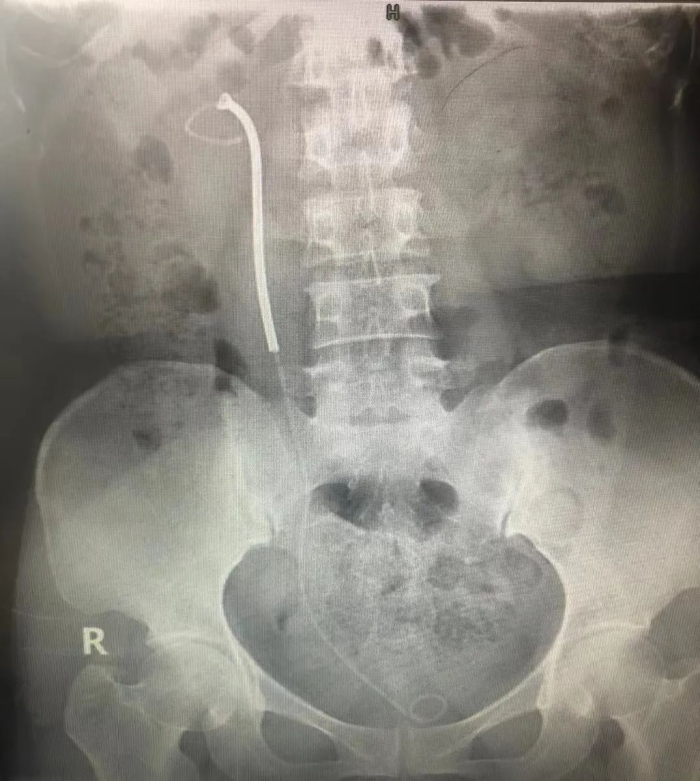

9月20日,在湘雅医院泌尿外科祖雄兵主任的指导下,贵阳市一医泌尿外科肖峰团队,采用双镜联合方式,成功为一位钬激光结石术后、肾内型肾盂狭窄、功能性孤肾女性患者置入了温控记忆合金永久支架(梅莫凯斯支架),彻底解决了困扰患者多年的输尿管狭窄问题。这是我省首例输尿管狭窄“温控记忆合金支架”置入手术。目前,患者状态良好,手术取得圆满成功!